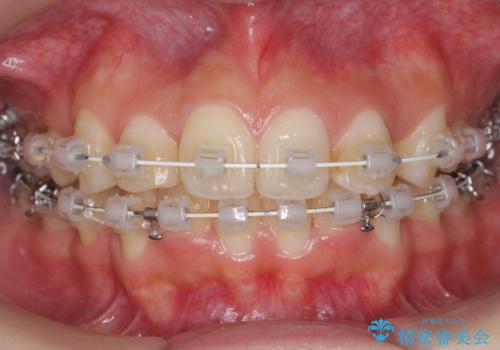

- ワイヤー矯正

- 前歯のがたつきを主訴に来院。

顔が小さく、顎に大きな歯が入りきらない状態でした。

抜歯してワイヤー矯正を行いました。